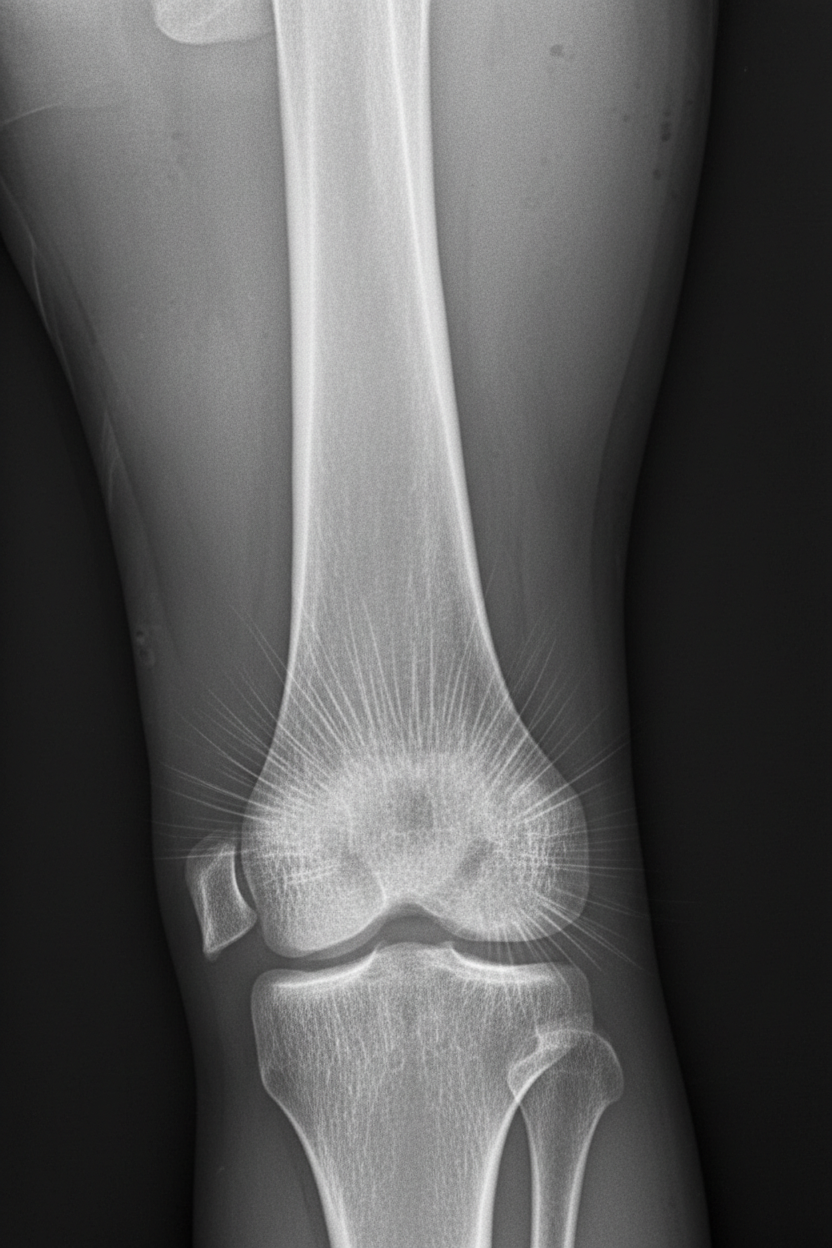

A 13-year-old boy is brought to his pediatrician for evaluation of leg pain. Specifically, he has been having pain around his right knee that has gotten progressively worse over the last several months. On presentation, he has swelling and tenderness over his right distal femur. Radiographs are obtained and the results are shown in figure A. His family history is significant in that several family members also had this disorder and others had pathology in the eye near birth. The patient is referred for a genetic consult, and a mutation is found on a certain chromosome. The chromosome that is most likely affected also contains a gene that is associated with which of the following pathologies?